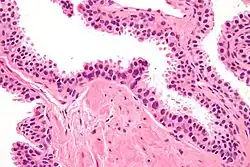

Histopathology of high-grade prostatic intraepithelial neoplasia (HGPIN) with typical features, H&E stain.[6]

High-grade prostatic intraepithelial neoplasia.

HGPIN typically has one of four different histologic patterns:[2]

Its cytologic features are that of prostatic adenocarcinoma:

Microscopically, PIN is a collection of irregular, atypical epithelial cells. The architecture of the glands and ducts remains normal. The epithelial cells proliferate and crowding results in a pseudo-multilayer appearance. They remain fully contained within a prostate acinus (the berry-shaped termination of a gland, where the secretion is produced) or duct. The latter can be demonstrated with special staining techniques (immunohistochemistry for cytokeratins) to identify the basal cells forming the supporting layer of the acinus. In prostate cancer, the abnormal cells spread beyond the boundaries of the acinus and form clusters without basal cells. In HGPIN, the basal cell layer is disrupted but present. PIN is primarily found in the peripheral zone of the prostate (75-80%), rarely in the transition zone (10-15%) and very rarely in the central zone (5%), a distribution that parallels the zonal distribution for prostate carcinoma.[7]

Several architectural variants of PIN have been described, and many cases have multiple patterns. The main ones are tufting, micropapillary, cribriform, and flat. Although these different appearances may cause confusion with other conditions, they have not been found to be of clinical importance. Rarer types are signet-ring-cell, small-cell-neuroendocrine, mucinous, foamy, inverted, and with squamous differentiation.[3]